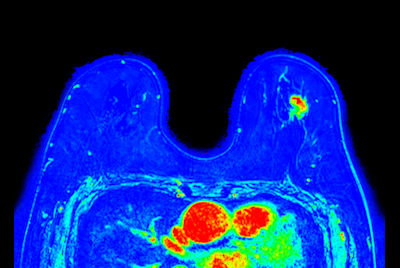

Breast Ca with T1 perfusion